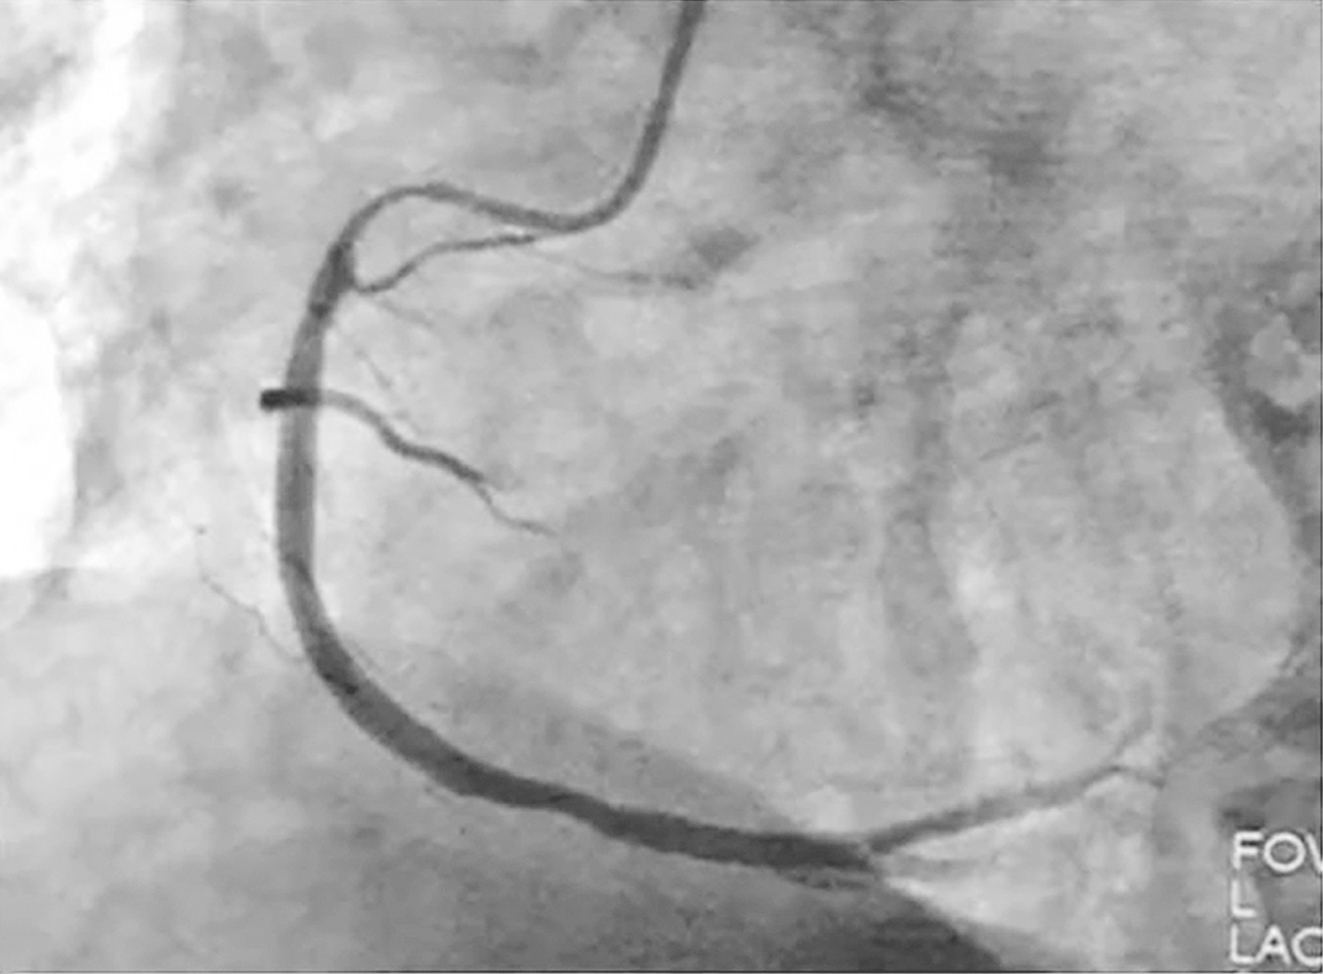

笔者单位冠脉造影:冠心病,冠脉三支严重病变,前降支中段第一对角支发出后闭塞,回旋支中段第一钝缘支发出后闭塞,右冠脉开口处狭窄95%(图2)。

图2冠脉造影显示冠脉三支严重病变